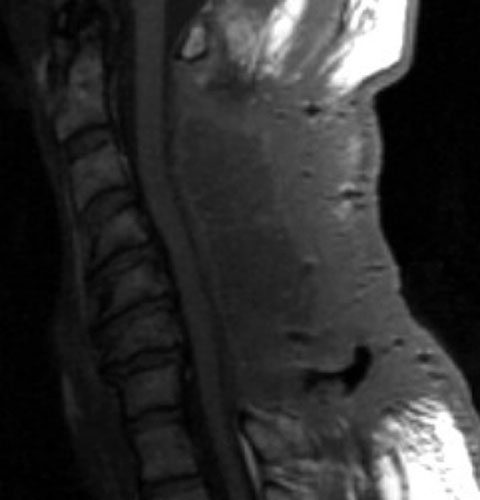

Seroma and Epidural Scar

A B